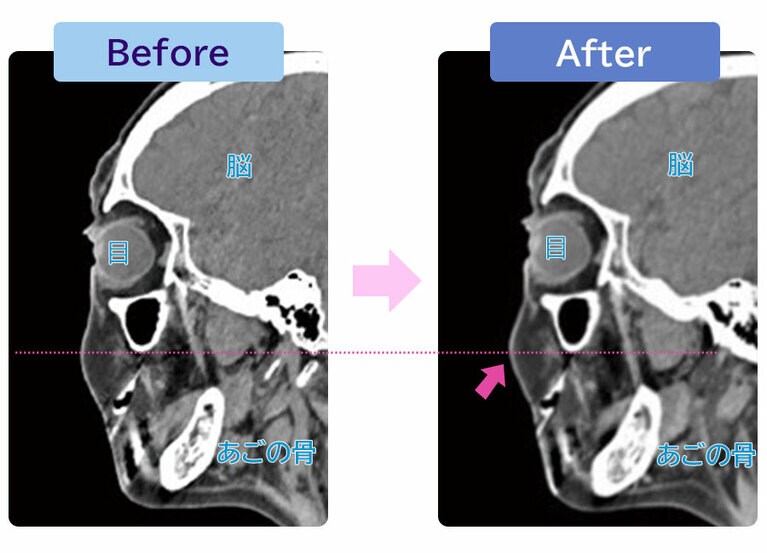

『目元のクマ・たるみ解消法』(内外出版社)。 奥田逸子先生。 奥田逸子先生。 表情筋の名称。赤い丸で囲ってある筋肉が、顔の若さに関係する。※画像は『目元のクマ・たるみ解消法』(内外出版社)より。 スマートフォンを見るときは目線まで持ち上げて、うつむかず、首に力を入れる。「うつむくと、頭の前の方に重力がかかり、筋肉がダラーンとしちゃいます」(奥田先生)。 奥田逸子先生。 60代女性のCT画像。ビフォー(左)と比べて、表情筋エクササイズを続けた後のアフター(右)は、頬の位置が上がり、厚みも増している。